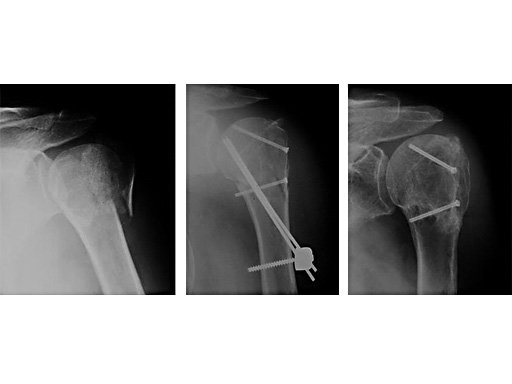

62 year old female patient

Fig 2

postoperative

Fig 3

Fracture healed